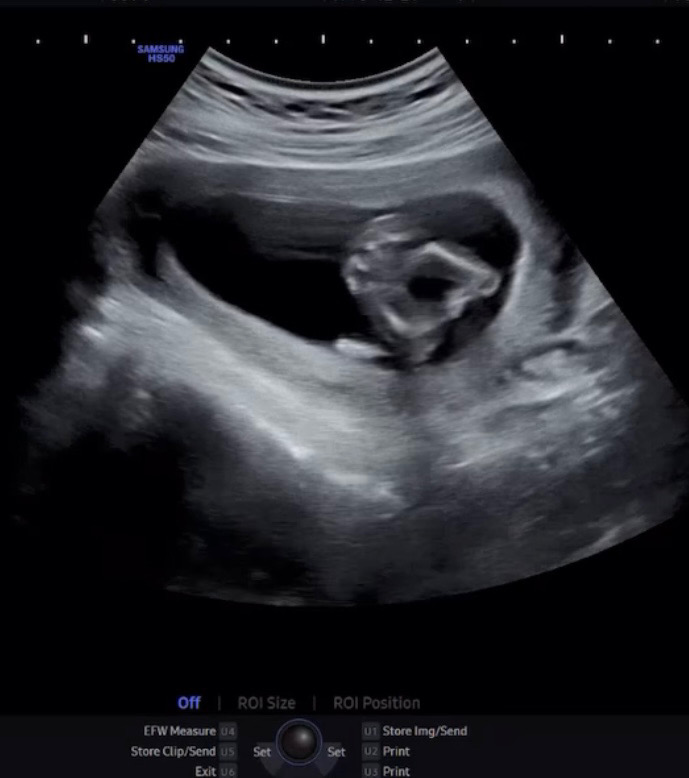

14주 🌶️가 안보이는데..딸일까용..?

사진은 아가 다리에요! 오늘 촘파보고왔는데 곧휴가 안보여요 딸일확률이 높은건가용?? 의사샘은 아직 16 20주 되봐야안다고 말씀을 앙해주셔서.. ㅎㅎ 어때보이시나요 🧐

헐 아무것도 없는거보니 딸인거같아요 아래에서 궁디를 보는 각도죠?

네 맞아요 아래에서 엉덩이 다리에요!!🤣